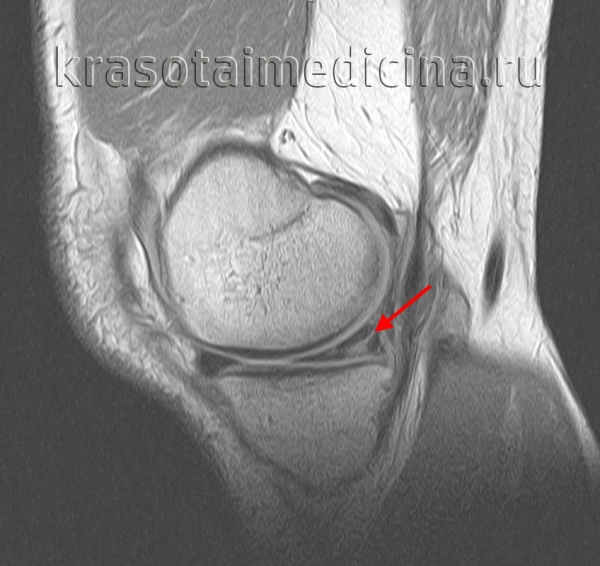

(Справа) МРТ Т2ВИ, режим подавления сигнала от жира, сагиттальный срез: у этого же пациента определяется гиперинтенсивный сигнал от разрыва и темная ткань мениска на периферии разрыва. Периферический ВПР может быть с легкостью определяться на последовательностях чувствительных к жидкости. (Слева) MPT PDBИ, сагиттальный срез: определяется вертикальный продольный разрыв заднего отдела медиального мениска. Этот разрыв немного смещен. Небольшой периферический фрагмент мениска позволяет отличить данный разрыв от отделения мениска от капсулы.

(Справа) МРТ PDВИ, режим подавления сигнала от жира, аксиальный срез: у этого же пациента определяется продольное направление разрыва, распространяющаяся через задний рог медиального мениска. Разрыв распространяется в заднюю ветвь мениска. (Слева) МР-артрография, Т1, коронарный срез: определяется вертикальный продольный разрыв медиального мениска с небольшим смещением. Этот разрыв возник в области перехода красной зоны мениска в белую.